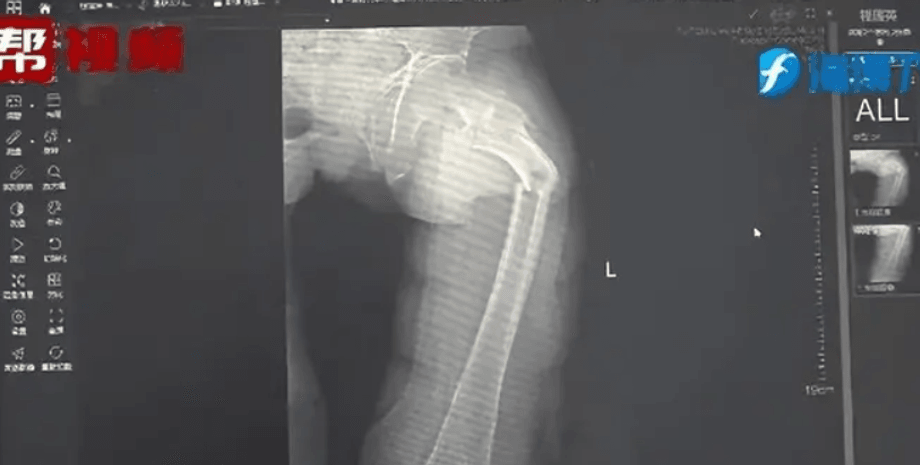

стегнова кістка, рентген, перелом

Рентген показав перелом стегнової кістки у пана Є | Фото: Oddity Central

Рентген показав, що у пана Є перелом стегнової кістки. Його історія про кашель не відповідала жодним фізичним травмам. Лікар Чжун та його команда вирішили провести додаткове обстеження. Вони розпитали пацієнта про його загальний стан здоров'я, харчові звички та спосіб життя, а також провели тест на щільність кісткової тканини, який продемонстрував тривожні результати. Показники 35-річного чоловіка відповідали нормі 80-річного. Ці результати є незвичними навіть для сучасних малорухливих людей.